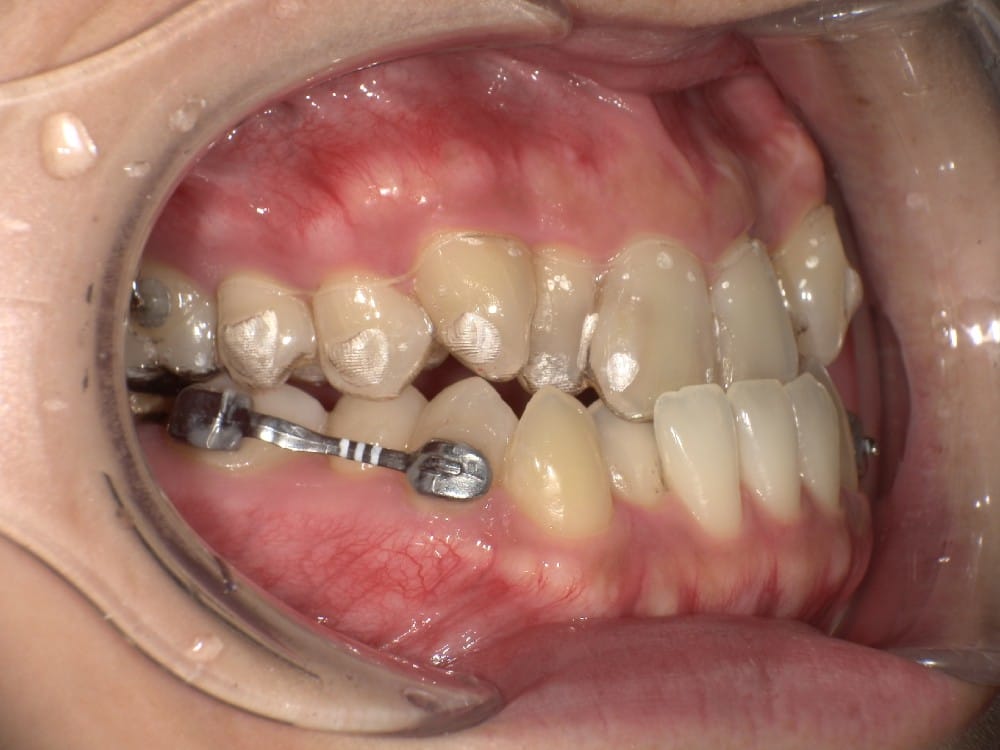

最後の画像のように奥歯のズレが1本以上あるケースでは、歯列矯正のみでの受け口の改善は困難と判断することが多いです。

このような奥歯の移動量が大きい症例では、マウスピースだけでは難しいことがあり、カリエールとよばれる装置を補助的に使用し、上下の噛み合わせの前後関係を整えることで、手術を行わずに機能面と見た目の両方が改善することがあります。

一時的に前歯は噛み合わせが開いていますが、受け口の矯正では、最終段階で前歯ばっかりあたって奥歯がしっかり噛まないということも起こりやすいので、あえて狙って動かしています。

今回のケースも奥歯の移動量が大きいため、マウスピースだけでは難しいと判断し、カリエールとよばれる装置を補助的に使用し、上下の噛み合わせの前後関係を整えることで、手術を行わずに機能面と見た目の両方が改善することにしました。

カリエール(CarriereMotion)とは?受け口矯正での役割

カリエール(CarriereMotion)は、噛み合わせの前後関係を整えるための補助装置です。

主に受け口(反対咬合)や出っ歯など、上下の噛み合わせにズレがあるケースで使用されます。

歯並びを細かく整える装置ではなく、矯正治療の初期段階で「土台となる噛み合わせ」を作ることが主な目的です。